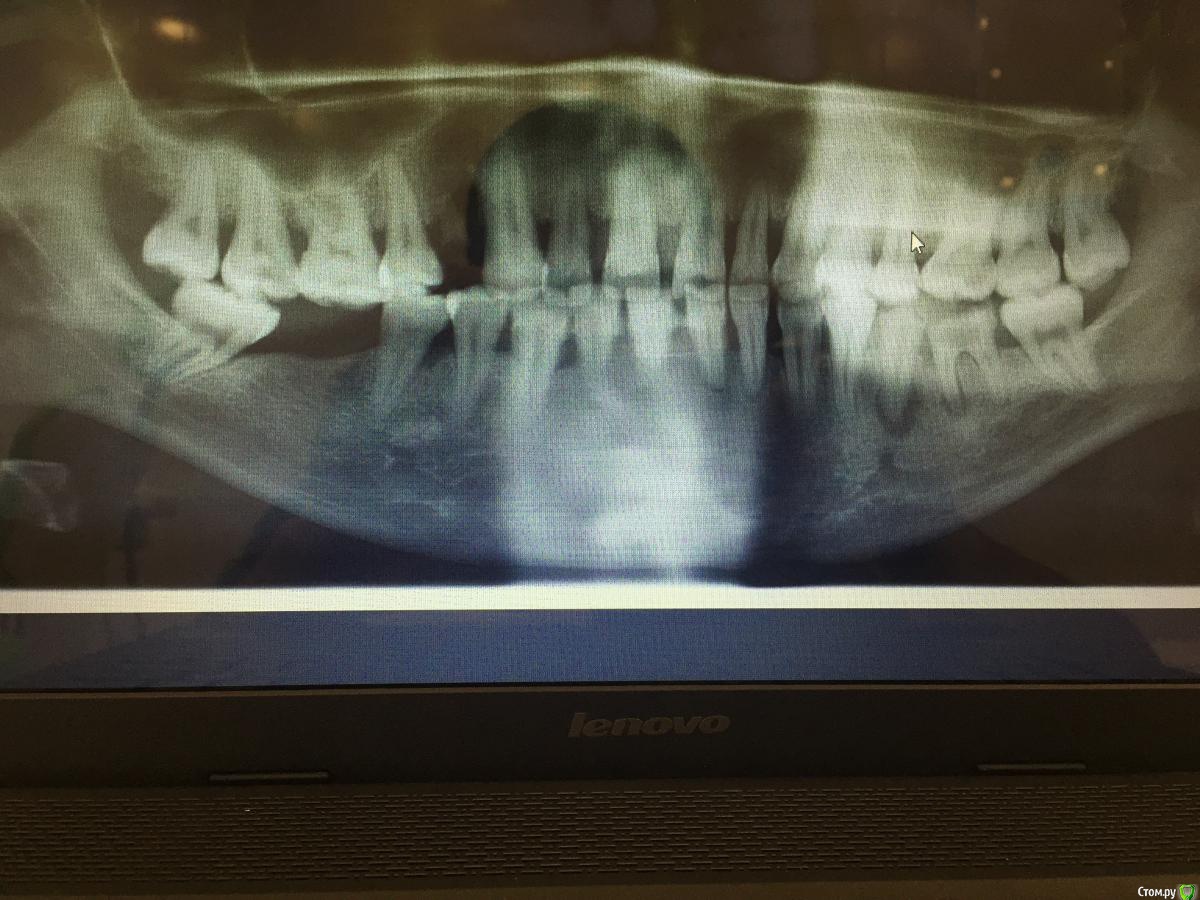

Денис777 Опубликовано 2 февраля, 2015 Автор Поделиться Опубликовано 2 февраля, 2015 Пациент пришел по поводу эстетического не удовлетворения своих зубов. Вееро образное расхождение фронтальных зубов,подвижность 2 степени.Нужен совет докторов кто как борется с пародонтозом,протокол лечения.P.S Извиняюсь за фото не было времени перекинуть в электронном ввиде Ссылка на комментарий

art700 Опубликовано 2 февраля, 2015 Поделиться Опубликовано 2 февраля, 2015 Ну ОПТГ здесь мало, фото и модели нужны. Ссылка на комментарий

Денис777 Опубликовано 4 февраля, 2015 Автор Поделиться Опубликовано 4 февраля, 2015 (изменено) Вот Доктора!!!Вчера получилось сделать фото и скинуть нормальное орто.. Изменено 4 февраля, 2015 пользователем Денис777 Ссылка на комментарий

krokomot Опубликовано 17 февраля, 2015 Поделиться Опубликовано 17 февраля, 2015 (изменено) Вариантов много, на что настроена сам пациентка, просто терапию и ли по полной программе голивуд? Из этого и вытекает бюджет. Учитывая узуру от поедания семечек он довольно скромный. Нужны все специалисты терапевты, хирурги, ортопеды( вряли она наденет бреккеты, а без них зубы обратно не задвинешь). Лечение каналов зубов с апекальным переодонтитом, удаление зубов со значительной атрофией. Протезирование боковых и фронтального отделов + конечно же регулярная переодонтальная поддерживающая терапия. Так получится что-то более менее вменяемое, за что стыдно не будет Изменено 17 февраля, 2015 пользователем krokomot Ссылка на комментарий